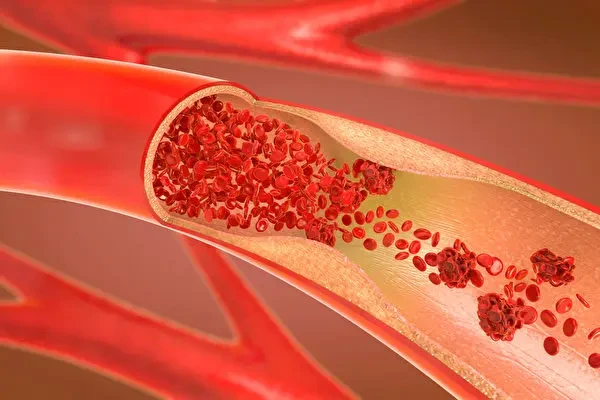

要是血管出現異常膨出,就好比路上突然冒出個大坑,車輛行駛到這兒就得減速、繞行,血液也容易在這些地方形成血栓,進而引發嚴重後果。

走行平直,沒有病理性彎曲:血管走行平直,是血液順暢流動的基礎。

要是血管像蜿蜒的山路,血液流動就會受阻,壓力增大,心臟就得加大 「馬力」 工作。

長此以往,心臟負擔加重,各種問題也就接踵而至。

已確診心腦血管疾病者,建議每 3 - 6 個月監測血脂變化。

這就好比給生病的血管裝上一個 「實時監控」,隨時掌握病情動態,調整治療方案。